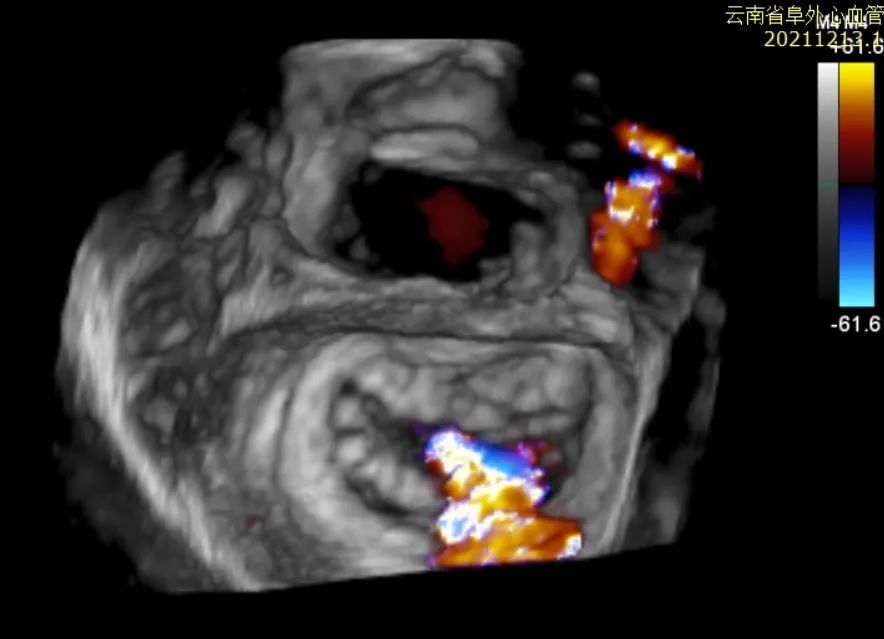

图2:术前3D Color TEE提示重度功能性二尖瓣反流

患者为63岁男性,罹患多支冠心病,既往发生急性心肌梗死,并曾接受两次PCI手术,存在缺血性心脏病继发的重度二尖瓣功能性反流。患者虽接受了最佳药物治疗且药物剂量已经调整到最大耐受剂量,但仍有明显症状,反复因心衰发作住院治疗,纽约心功能III级,且合并高血压、肾功能不全、室性早搏等合并症。超声(TTE/TEE)提示重度功能性二尖瓣反流(4+),缩流颈宽约7x15mm,有效反流口面积约0.67cm2;全心扩大(左室舒张末前后径62mm),左室壁运动幅度明显减低,LVEF 31%,二尖瓣前后叶活动尚可,瓣叶未见明显挛缩及活动受限,合并三尖瓣反流及肺动脉高压。患者STS评分8.92分,外科手术风险高危。心脏团队经过对患者病情和二尖瓣解剖的全面评估与讨论,决定采用JensClip瓣膜夹系统为患者进行二尖瓣缘对缘修复手术,以改善患者的二尖瓣反流及临床症状。